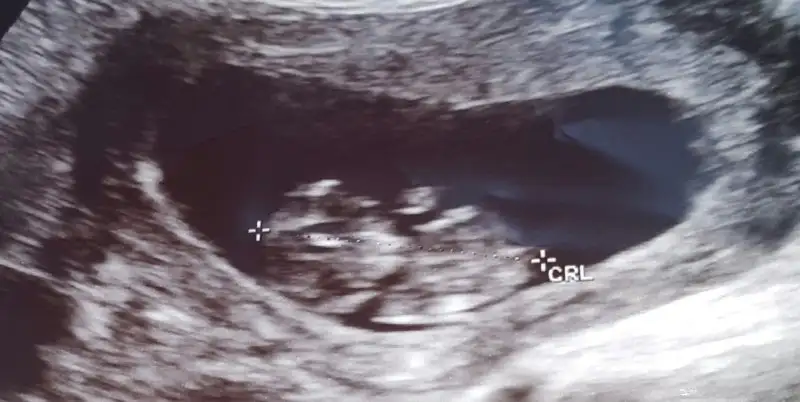

Bu arada 8.hafta icin ultrason kagidi olanlar varsa cinsiyet tahmini yapabiliriz .benim kizda tuttu.

Birde cinsiyet tahmini nasil oluyor benim 6+6 lik usg goruntum var :)